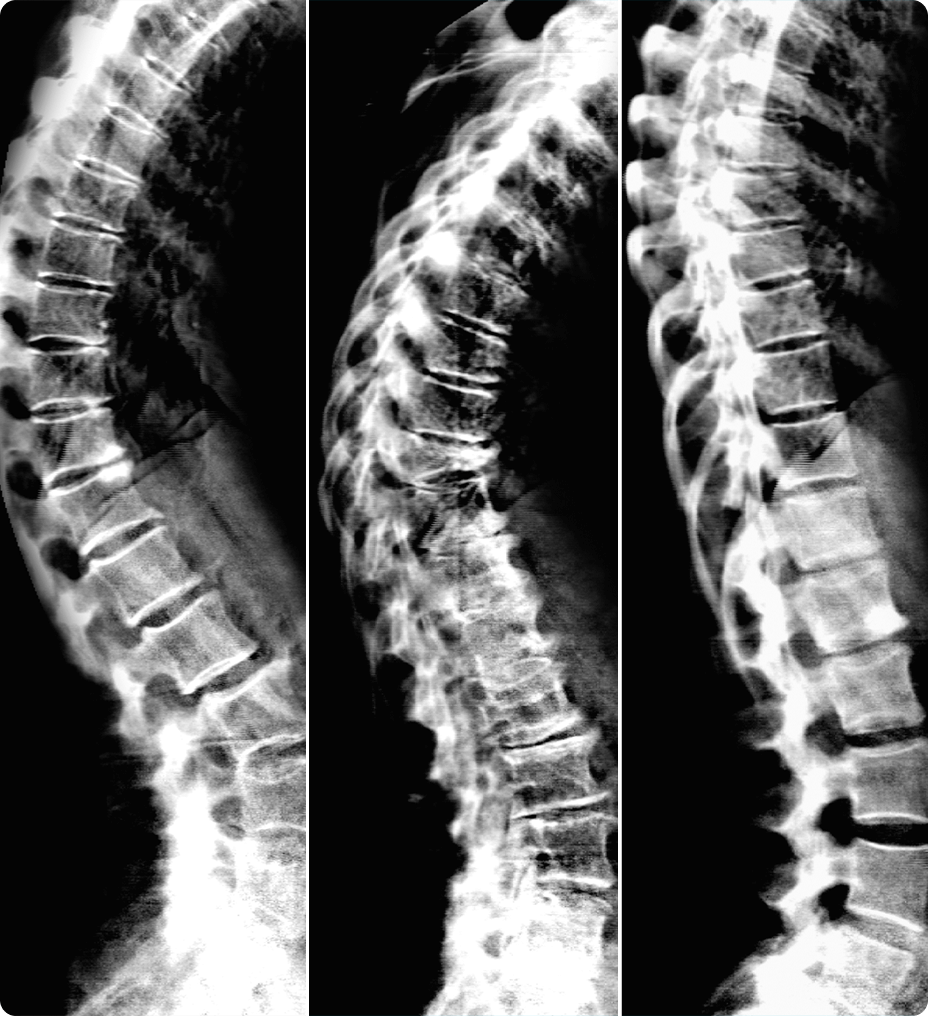

Nell’ambito oncologico, l’imaging di diffusione svolge un ruolo centrale. SIGNA™ Sprint permette di ottenere immagini più nitide, con una riduzione delle distorsioni e un SNR ottimizzato.¹

Il progressivo aumento delle esigenze diagnostiche in ambito oncologico e cardiologico richiede una risonanza magnetica capace di garantire qualità costante anche negli scenari più complessi. Con prestazioni del gradiente pari a 65/200, SIGNA™ Sprint offre immagini estremamente nitide e contribuisce a migliorare la sicurezza diagnostica. Il miglioramento del rapporto segnale‑rumore (SNR), l’evoluzione delle applicazioni di diffusione e l’impiego di soluzioni basate su deep learning ampliano le capacità diagnostiche e permettono di monitorare in modo più accurato la risposta terapeutica nei pazienti oncologici.¹